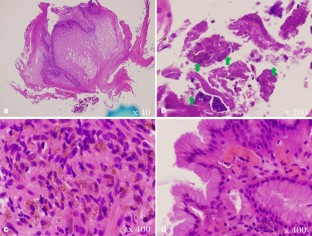

Fig. 1